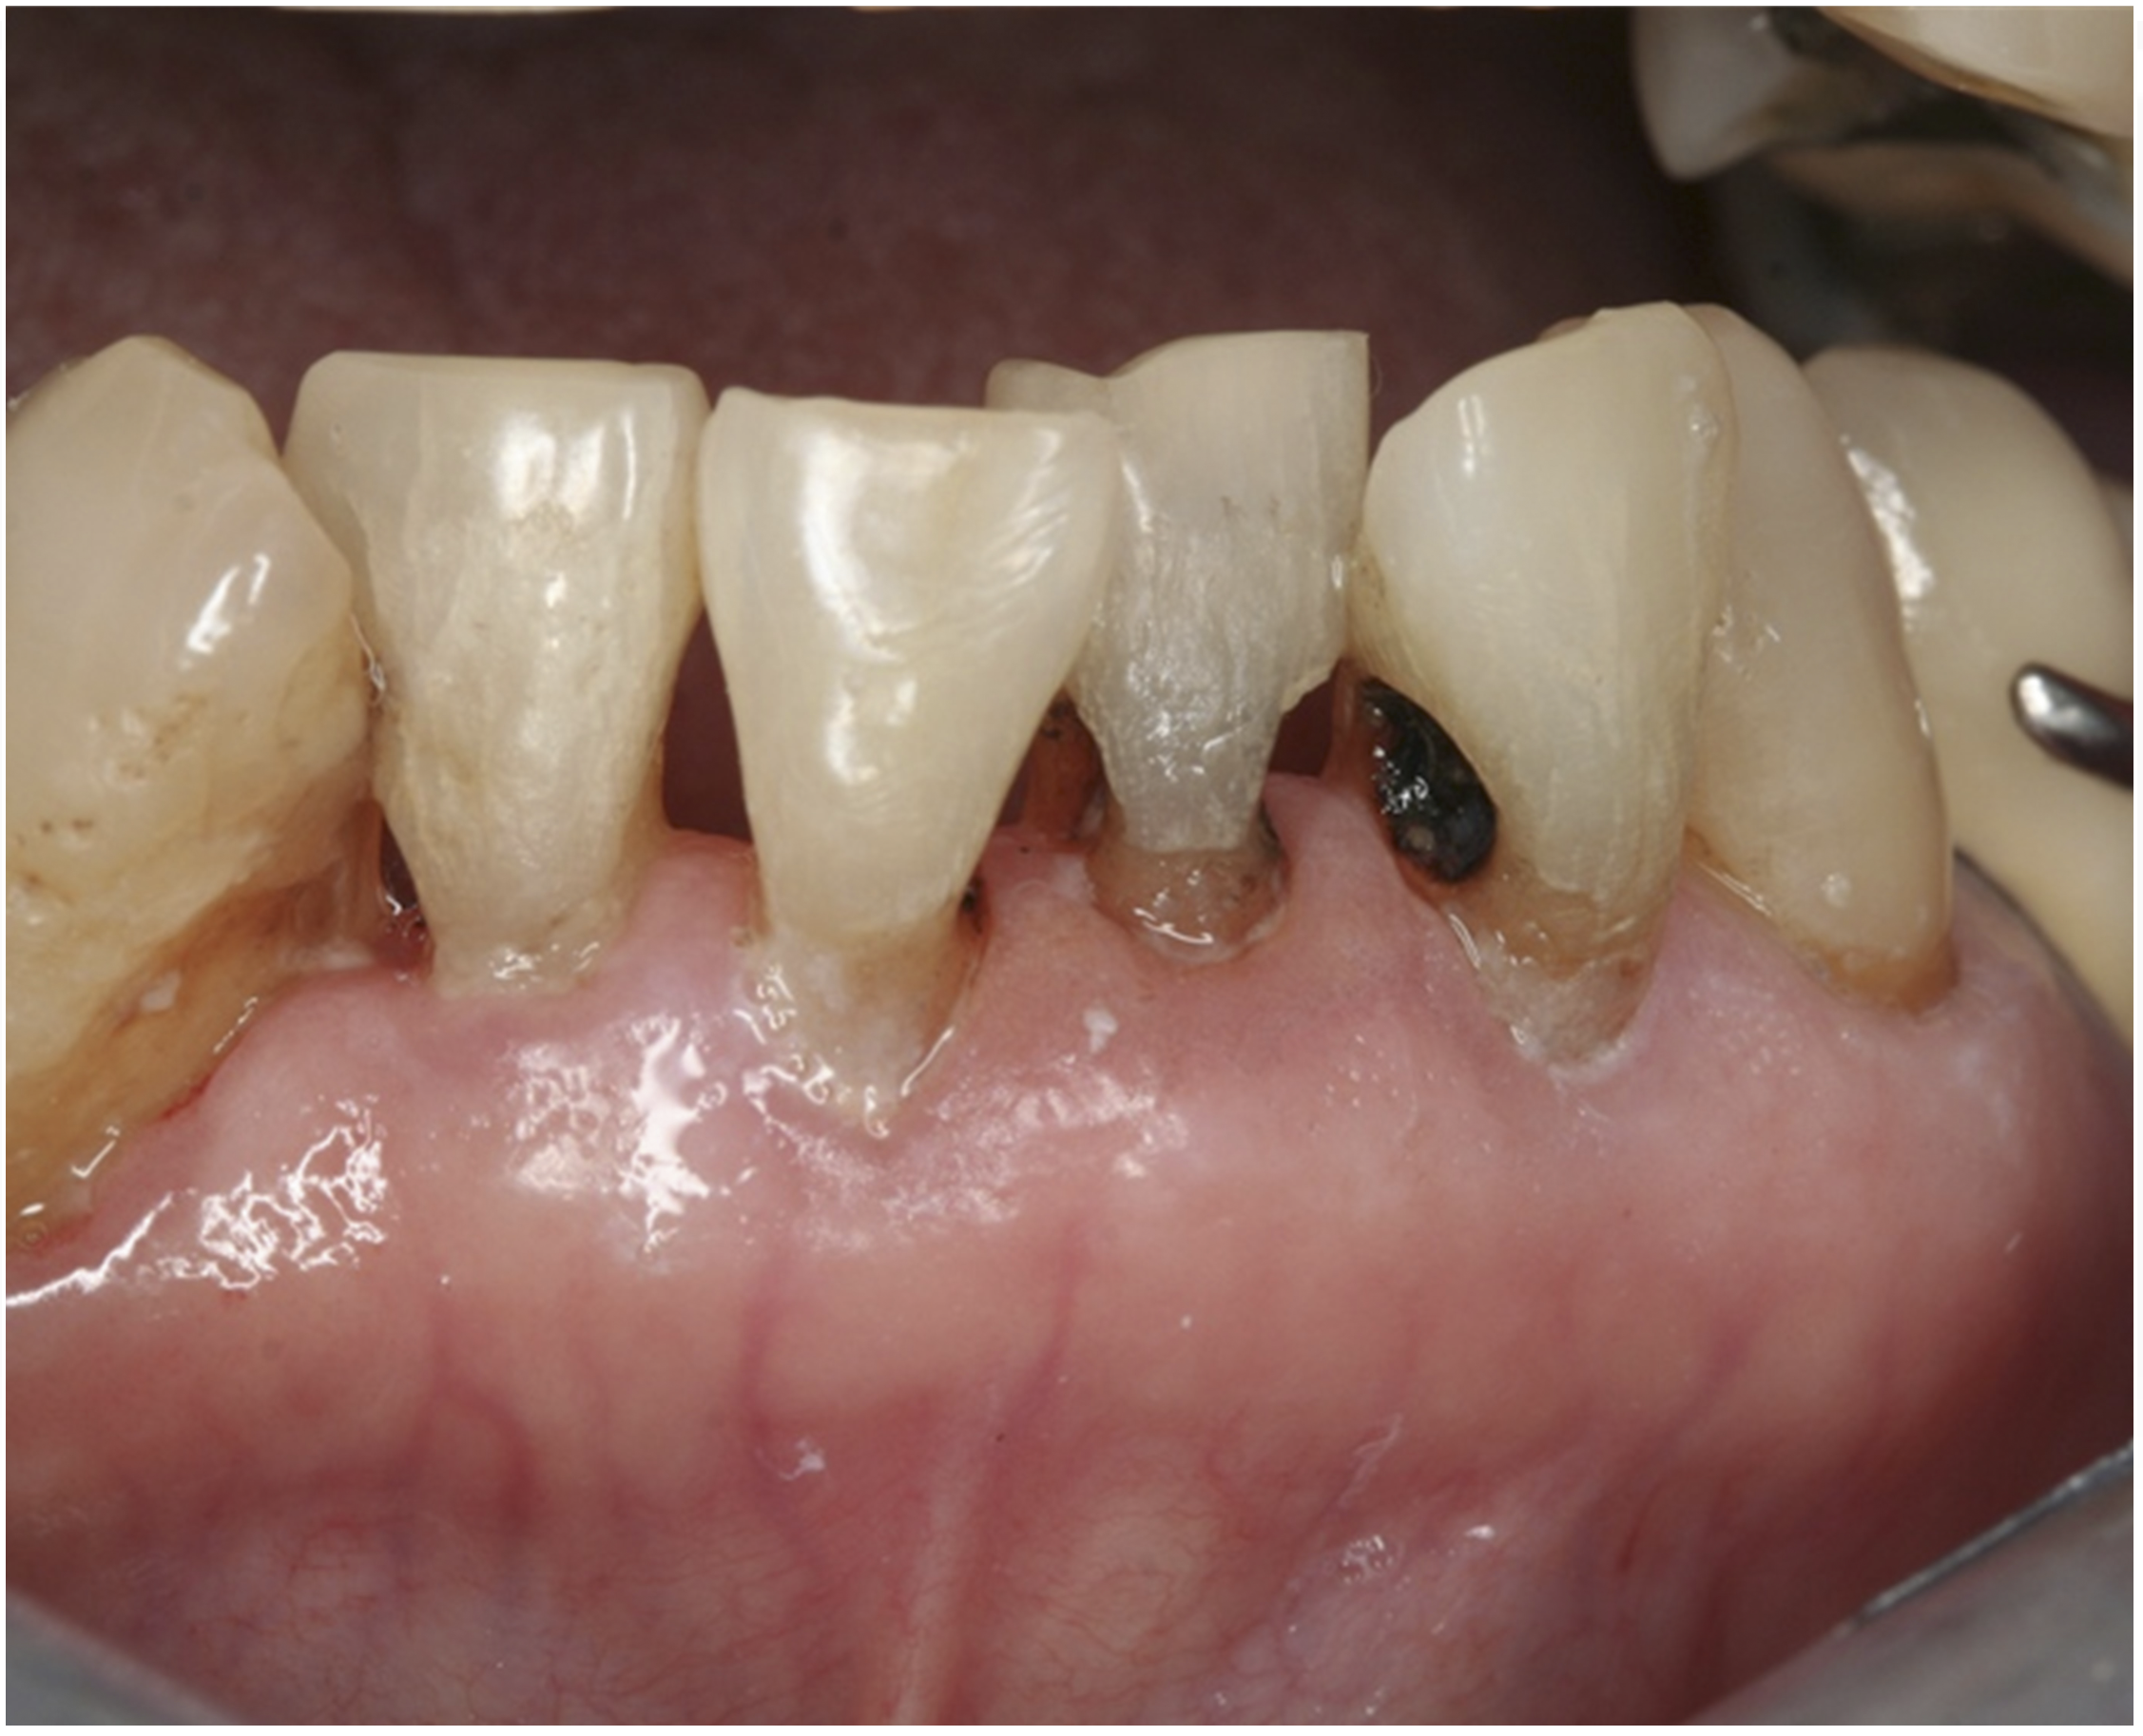

There are several advantages of using SDF in dental treatment. First, it showed an antimicrobial activity against mono-species, dual-species, and multi-species cariogenic biofilm.14-16 Silver ions are bactericidal metal cations that inhibit biofilm formation.17 Studies have indicated that silver interacts with sulfhydryl groups of proteins and DNA, thus altering hydrogen bonding and inhibiting respiratory processes, DNA unwinding, cell-wall synthesis, and cell division.18 At the macro level, these interactions affect bacterial killing and inhibit biofilm formation.17 Second, fluoride promotes caries lesion remineralization. Fluoride has been indicated to react with hydroxyapatite and generate calcium fluoride, which is a reservoir of fluoride, and facilitate further remineralization.19 An ex vivo study reported surface microhardness of the surface layer of the arrested caries after SDF applications was comparable with the unaffected sound dentin20 (Figure 1 and Figure 2). This is consistent with another study, in which a high remineralized zone was observed on the surface of arrested caries from exfoliated teeth with SDF treatment21 (Figure 3 and Figure 4). Third, its application procedures are simple and do not require injection or drilling, and the treatment does not involve expensive support infrastructure equipment such as piped water and electricity. The simplicity of the treatment is conducive to treating caries in apprehensive young children who may have intense dental fear, uncooperative patients with special needs, or elderly patients who have difficulty adapting to traditional dental care. It also allows trained workers to deliver the treatment to people who live in the area but who may not be able to easily access dental service.22 Patient compliance and satisfaction is often good when the patient is provided a clear explanation of the treatment outcome.23,24 Finally, the cost of SDF treatment is low and should be affordable in most communities.

Fig 1. Ground section of a primary incisor with arrested caries lesion after SDF treatment: arrested caries that had SDF treatment. (image from Chu and Lo, 2008, ref 20 [reprinted with approval])

Figure 1

Fig 5. Use of 38% SDF to arrest coronal caries in primary teeth of a young child. The arrested carious lesion had a hard, blackened, and impermeable layer.

Figure 5